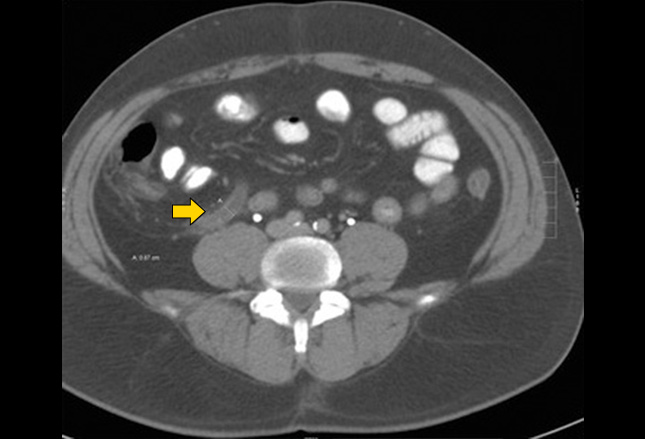

CT扫描描绘了肠系膜上静脉血栓形成的肠缺血。可见肠壁增厚(箭头)伴肠壁扩张。